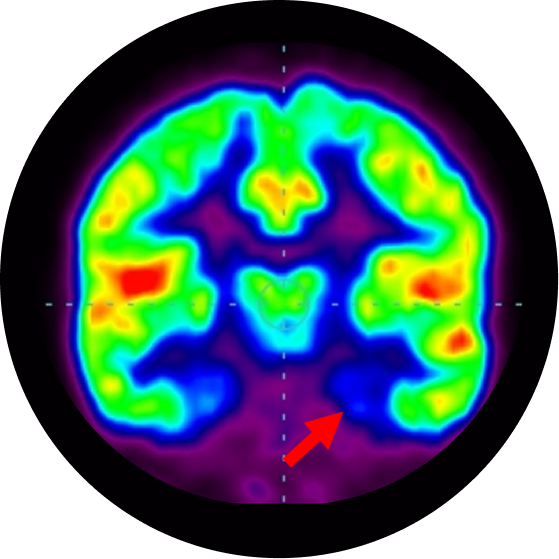

In autism, though the brain structure looks normal, there are functional abnormalities in specific regions of brain. This information, about the functioning of brain areas can be obtained from functional neuroimaging techniques like PET-CT scan and functional MRI scan of the brain. These imaging studies permit the study of the abnormal pattern of cortical activation in autism. These studies indicate that certain areas of the brain show reduced functioning like mesial temporal lobe (innermost part of the brain responsible for learning, understanding, memory, social interaction and abstract thinking), frontal lobe (the front part of the brain responsible for emotions and aggression) and cerebellum (responsible for balance, coordination, muscle tone and speech). Hence the dysfunction of these areas are responsible for problems seen in autism.

Positron Emission Tomography  Computed Tomography Scans showing areas of brain with reduced function

Medial Temporal Cortex

Cerebellum